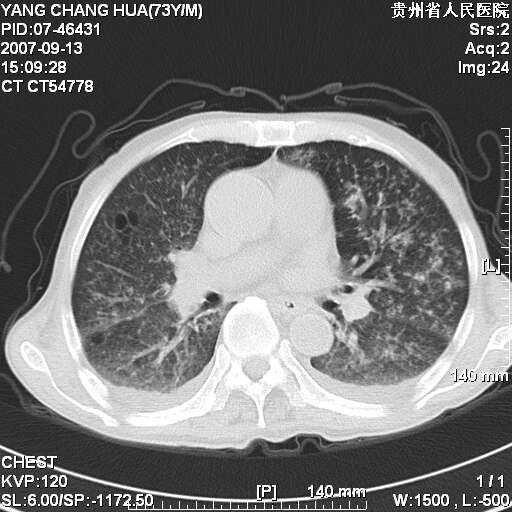

图像没有传全。肺部为感染性病灶;肺囊肿;双侧胸腔积液;肝脾肿大;腹水。

双肺部为感染性病灶.双侧胸腔积液;肝脾肿大;腹水.

双肺部为感染性病灶.双侧胸腔积液;肝脾肿大;脾脏密度不均,不除外脾侵润?腹水.

图片不全.就这几张图片.无法诊断淋巴瘤的,我考虑:双肺部为炎性病灶.双侧胸腔积液;肝脾肿大;腹水

双肺点片状影,以双上肺改变明显.双侧胸腔积液.为感染性病灶,但不除外结核.

肝脾都大..

双上肺继发型肺结核。

双侧胸腔积液。

肺大泡。

双肺散在斑片状及多发小结节状阴影,边缘模糊,双上肺野明显,双侧胸膜腔少量积液,纵隔及肺门区未见明显肿大淋巴结,肝脾肿大,脾内见多发低密度区,结合临床考虑恶性淋巴瘤(肺内表现为肺炎肺泡型),单看影像表现,肺结核不能排除。建议结合实验室检查或表浅淋巴结活检。

肺部为;恶性淋巴瘤;双侧胸腔积液;肝脾肿大;腹水。